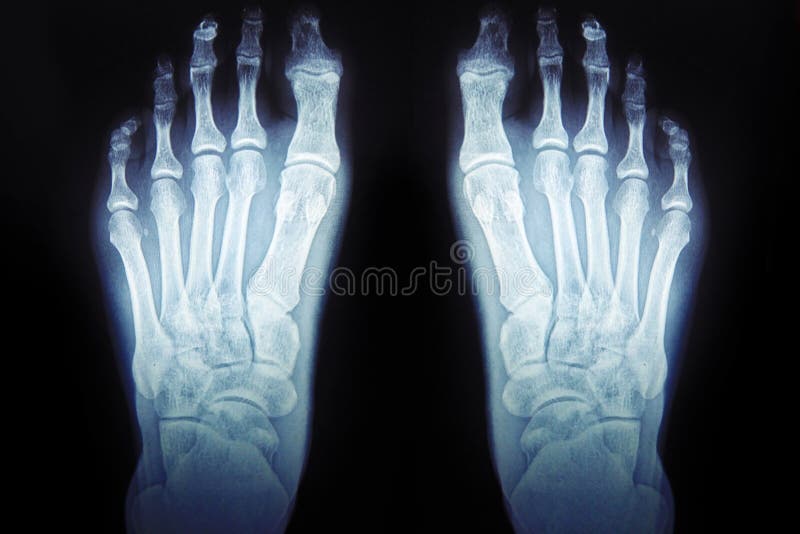

Human Foot Bones Xray . You can use radiopaedia cases in a variety of ways to help you learn and teach. The bones of the foot provide mechanical support for the soft tissues; The dorsoplantar view is part of a three view series examining the phalanges, metatarsals and tarsal bones that make up the foot. Helping the foot withstand the weight of the body whilst standing and in motion. These bones include your ankle bones. The image displays the soft tissues and bones of your foot. These bones give structure to the foot and allow for all foot movements like flexing. Share cases with the diagnosis hidden.